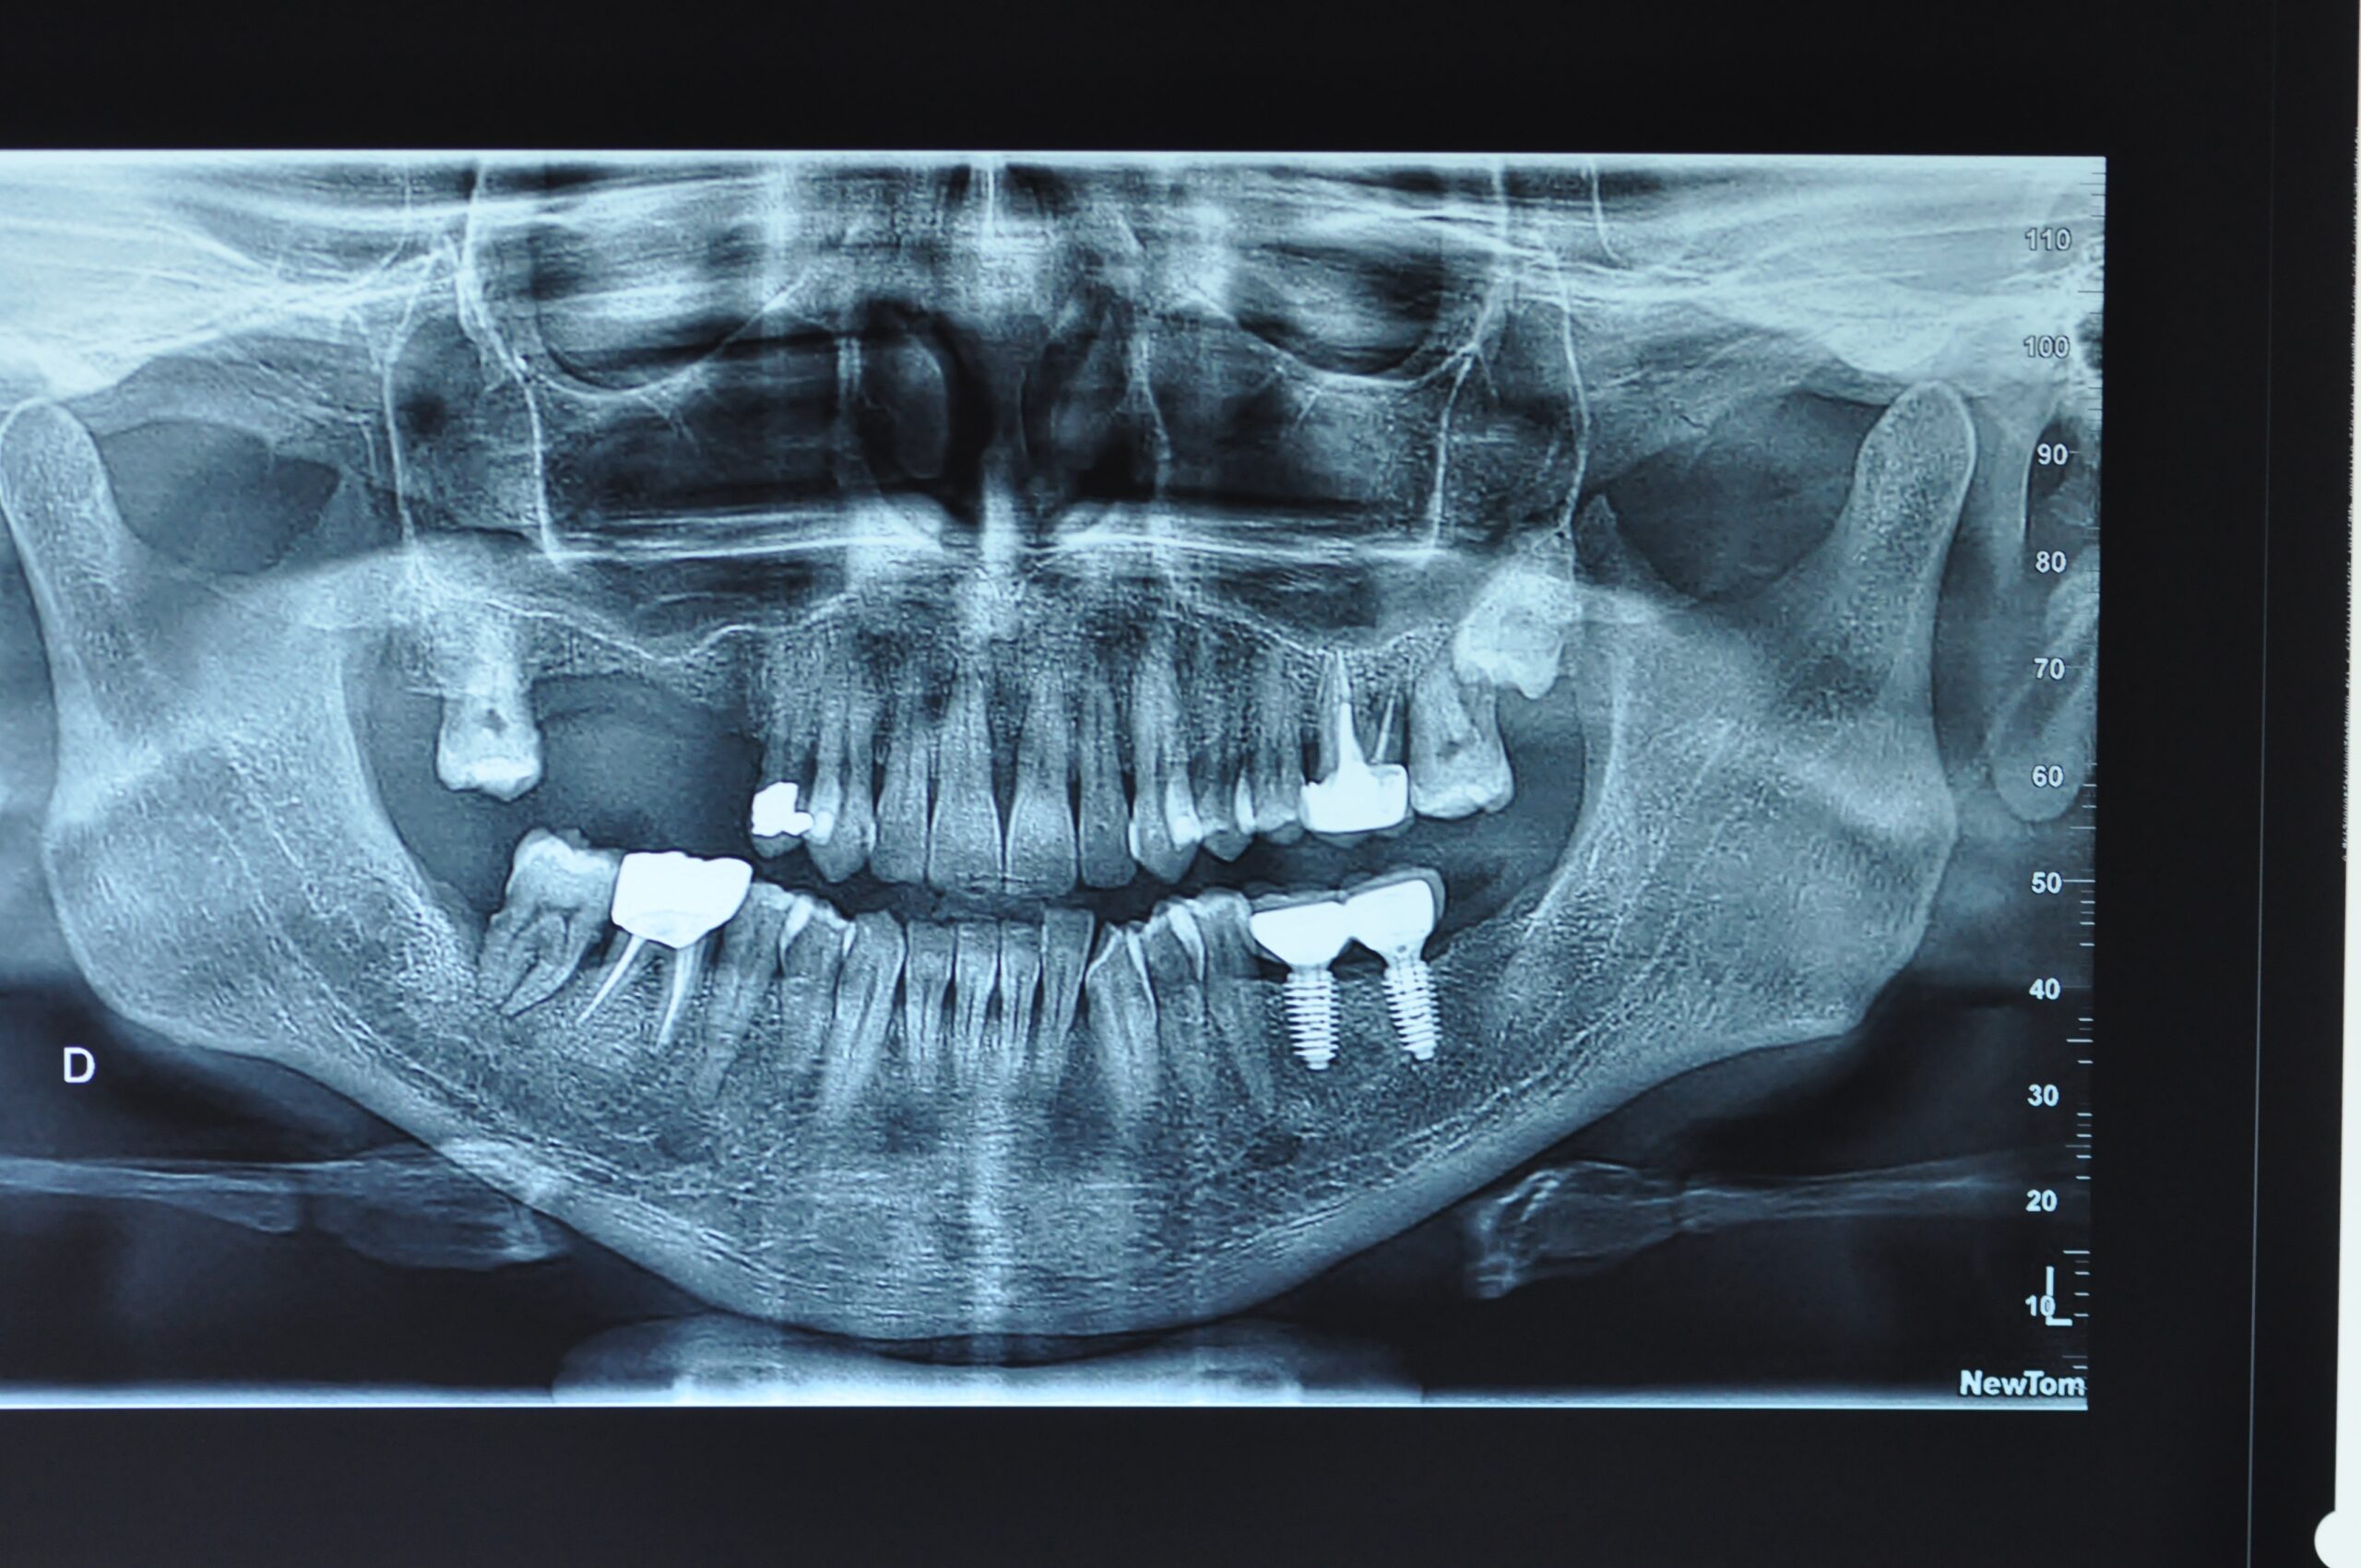

→ Pose de la prothèse définitive

Après la cicatrisation de l’os et de la gencive, une simple prise d’empreinte comme sur une dent naturelle permettra la réalisation d’une prothèse naturelle et fonctionnelle.

→ Entretien

Votre dentiste vous expliquera les soins et l’entretien nécessaires avec vos implants, avant, pendant et après le traitement. Il suffit de respecter des règles d’hygiène buccale quotidienne et de procéder régulièrement à des contrôles : vos implants auront alors l’aspect, la fonction et les sensations de vos dents naturelles pendant de nombreuses années.

La durée totale du traitement dépend de plusieurs facteurs. Il est déterminé en fonction du nombre de dents à remplacer, du volume osseux, de l’état général du patient. En général, il faut entre 3 et 9 mois.